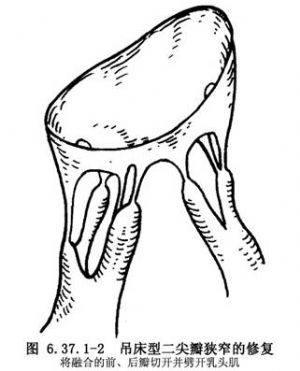

(2)吊床型:将融合的前、后瓣分开,经瓣口显露左心室腔。如显露困难,再从后瓣中部垂直瓣环切开瓣叶,充分显露瓣下结构。先切开前后乳头肌形成的拱桥,再沿腱索方向劈开乳头肌,并将多余的部分切除,以扩大左心室腔(图6.37.1-2),缝合后瓣切口。